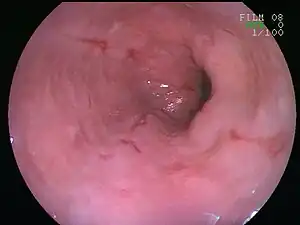

| An esophageal ulcer visualized by esophagoscopy: the reddened area at 10 o'clock on the surface of the mucosa. | |